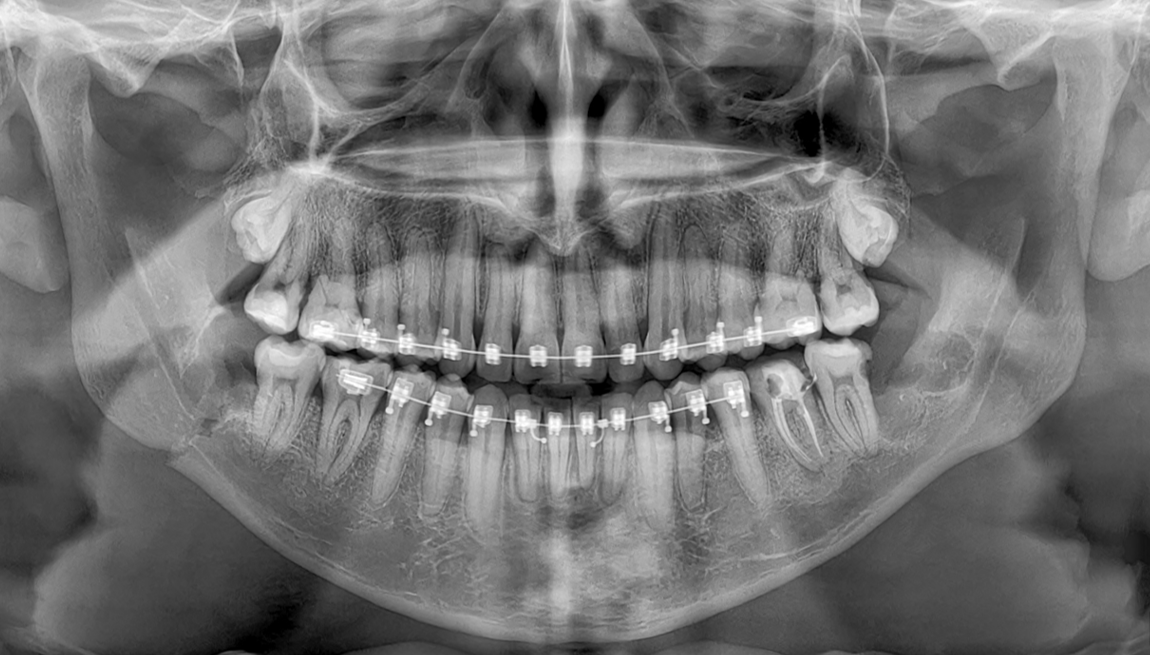

Caso Clinico N° 743 CANINOS RETENIDOS

3 Sep 2025